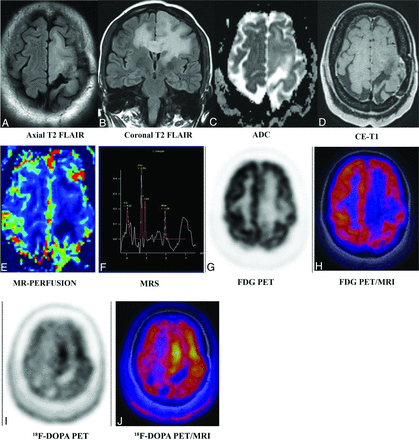

A 35-year-old man was initially diagnosed with left frontal lobe oligodendroglioma grade II, status post resection and chemoradiation in 2008. He underwent a follow-up [18F] DOPA-PET MR imaging. T2 FLAIR axial (A) and coronal (B) images demonstrate a large cortical and subcortical area of abnormal T2-FLAIR hyperintensity in the left parasagittal frontal lobe extending to the left gangliocapsular area and the corpus callosum and across the midline in the right parietal region without apparent diffusion restriction (C), enhancement (D), and increased rCBV perfusion (E). Multivoxel MRS (F) shows increased Cho/Cr and Cho/NAA ratios (1.86 and 2.31, respectively). FDG-PET MR imaging (G and H) shows no appreciable FDG uptake. FDOPA-PET MR imaging shows areas of significant DOPA tracer uptake (maximum standard uptake value = 1.54 versus <1.0 as normal) more prominently in the left paramedian frontal region. FDOPA-avid, FDG-nonavid nonenhancing lesion in the left frontal region involving the corpus callosum with positive MR imaging correlates suggests active underlying residual/recurrent disease. This case again highlights the superiority of AATs over FDG and the importance of multiparametric MR imaging over individual sequences. AAT uptake in the absence of contrast enhancement and increased perfusion helped with the planning of surgery and radiation. CE indicates contrast-enhanced.